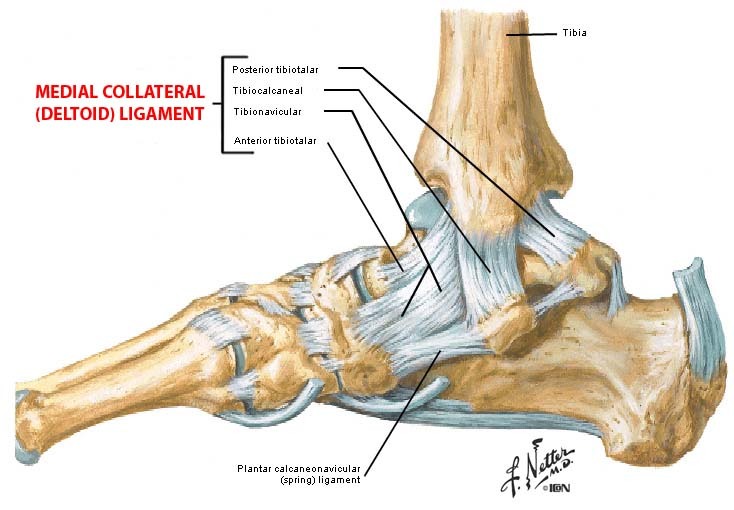

내측에 위치한 삼각인대가 매우 강하며 흔하지 않게 파열된다. 인대 파열보다는 외전 손상으로 대개 내측과의 견열 골절이 나타난다. 삼각인대는 네 개의 인대로 구성되는데, 표층에 둘, 심층에 둘로 이뤄져있다.

△ Medial Collateral (Deltoid) Ligament

(이미지 출처 : http://www.unmc.edu/dissection/idg35ankle.cfm)